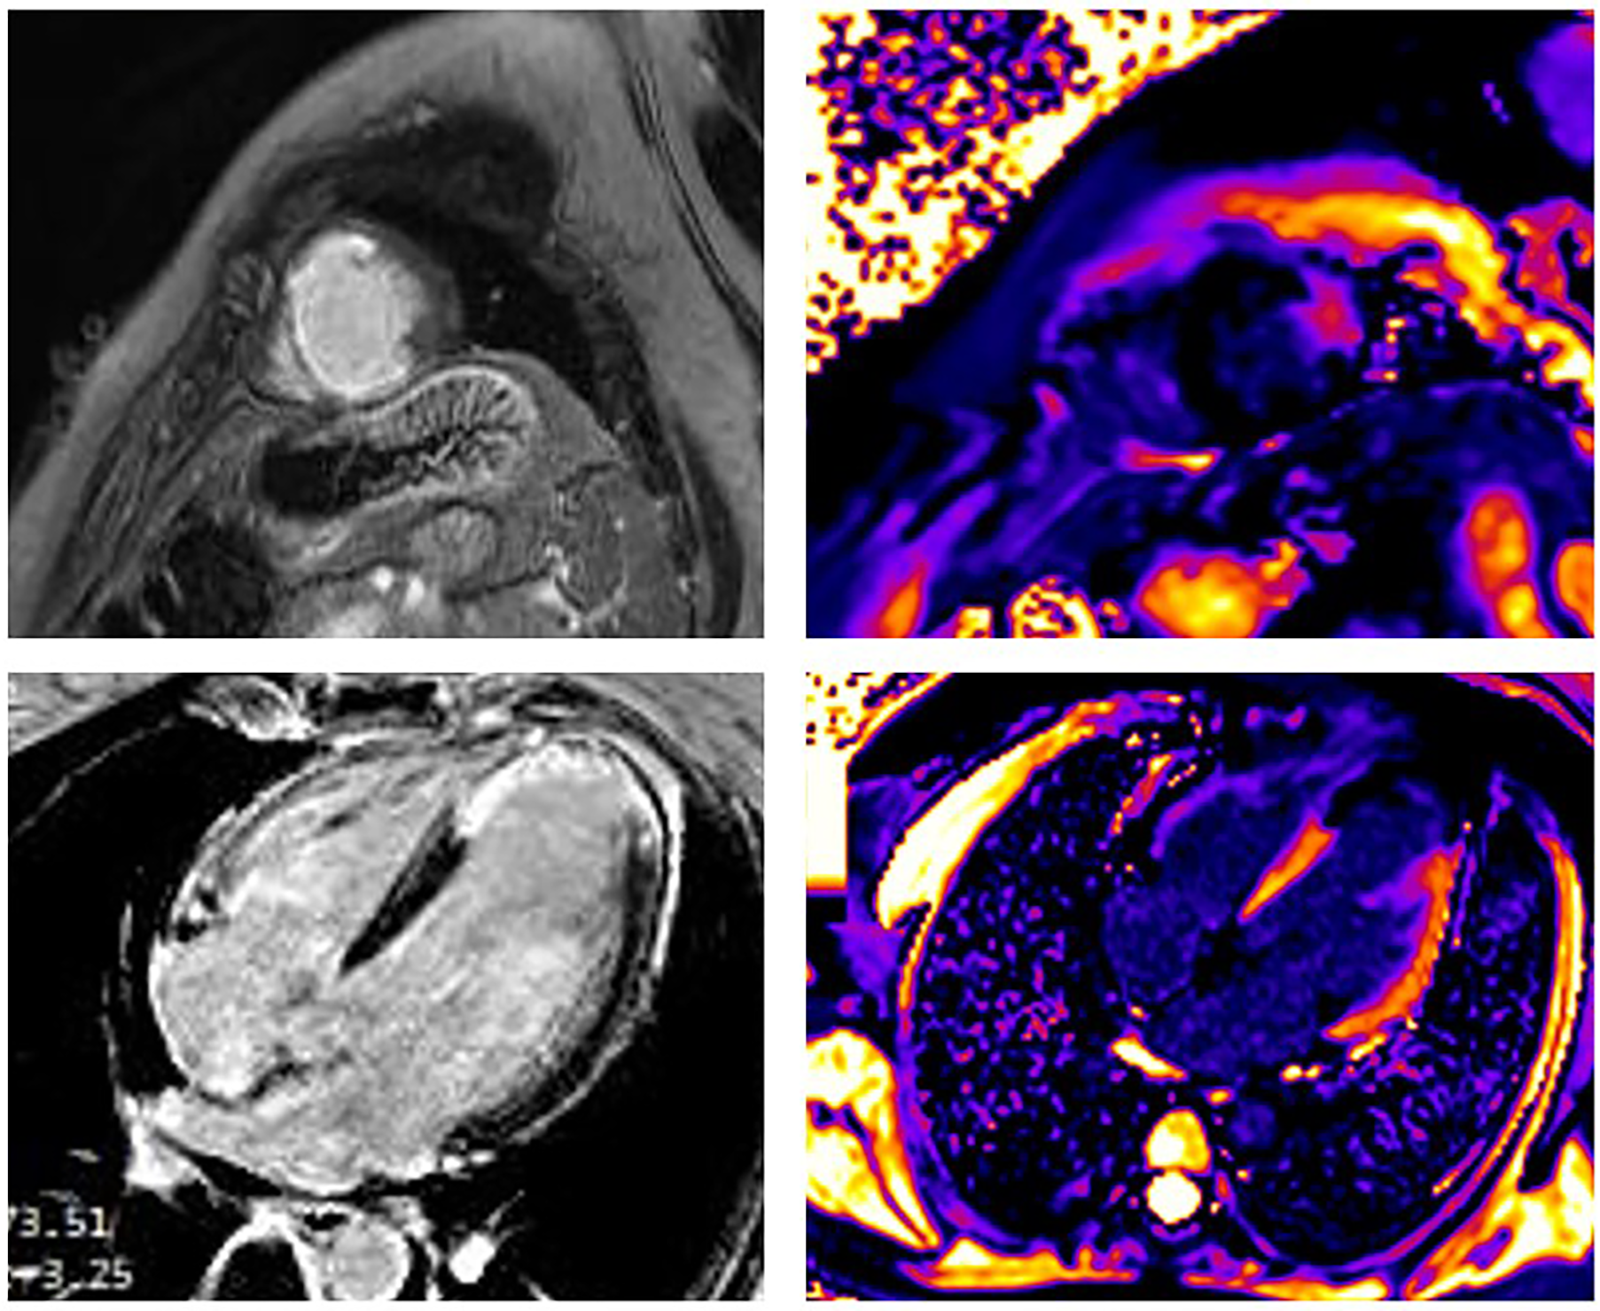

The occurrence of myocardial injury in SCAD, which presents as myocardial infarction, may not always be visible and depends on the type of SCAD. It is in accordance with thrombolysis in myocardial infarction (TIMI) flow and the speed of healing coronary disease. Figures 24 present three patients with different types of SCAD and myocardial infarct sizes, which depend on that.

FIGURE 2

www.frontiersin.org

Figure 2. A 42-year-old woman presented as STEMI anterior localization SCAD on left anterior artery type 4 and TIMI flow 0, treated with percutaneous transluminal coronary angioplasty (PTCA) without implantation of stents. Late gadolinium enhancement (LGE) was seen in the sub-endocardium in the medio-apical part of the septum apical parts of inferior and posterior walls and transmural in the apical part of the septum and anterolateral walls of LV. Post-contrast T1 mapping identified the zone of fibrosis, which was the zone of infarction and was also present in apical segments of LV. In addition, the peri-infarct area had a high T1 signal. The size of fibrosis (infarct size) was 13%.